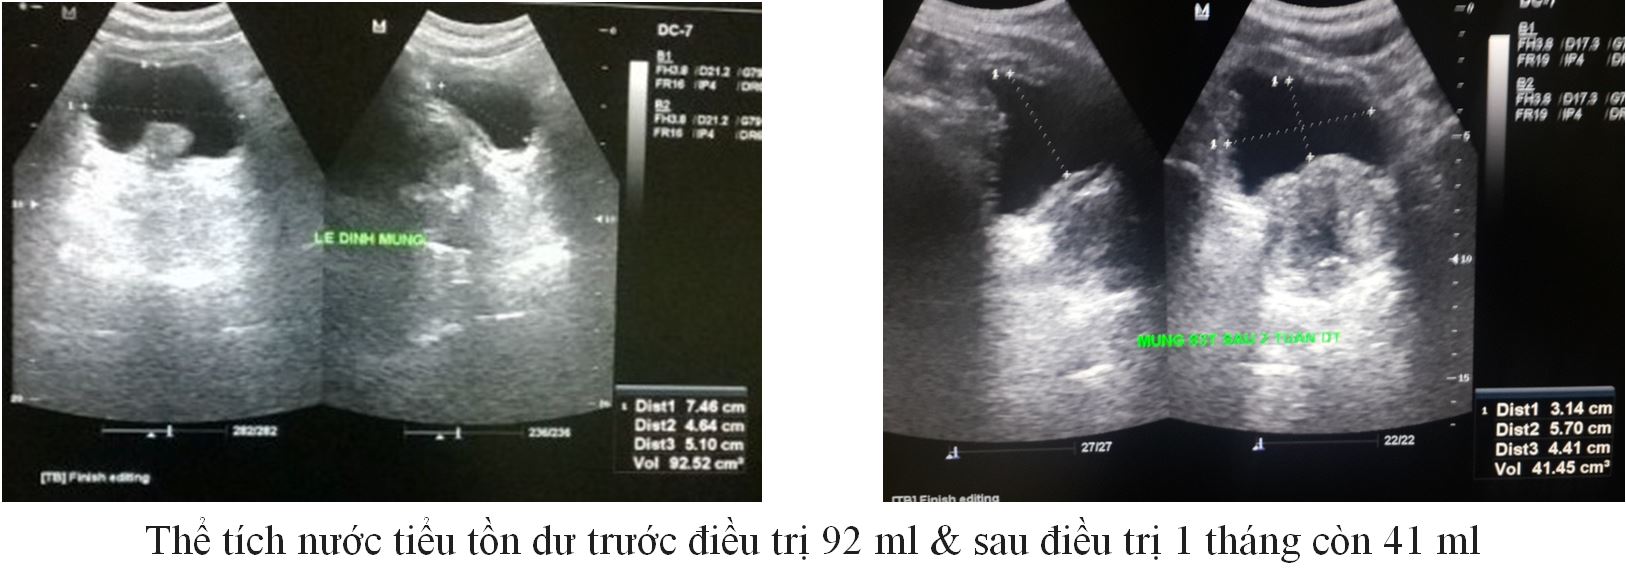

Trường hợp 1:

– BN M, 83 Tuổi

– Tiểu khó, nhiều lần ( liên tục trong đêm > 10 lần)

– Thể tích TLT 73 gam.

|

Trước ĐT |

Sau 1 tháng ĐT |

IPSS (Điểm) |

26 |

12 |

QoL (Điểm) |

4 |

2 |

PVR (ml) |

92 |

41 |

PV (gam) |

73 |

67 |

PSA (ng/ml) |

3,4 |

– |